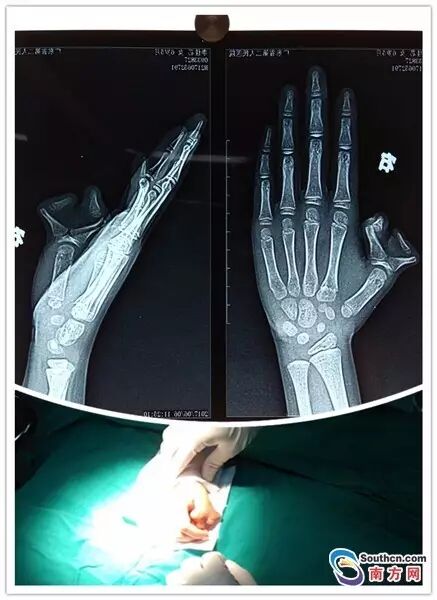

近日,广东省第二人民医院整形美容中心就收治了一名有着“蟹钳”手的小女孩朵朵(化名)。老家在汕头的朵朵今年6岁,出生时右手拇指就是多指畸形,拇指有主、副两个,状似蟹钳。

朵朵是汕头人,在她出生后,家长就发现朵朵右手拇指根部多出一块肉团,随着时间的推移,肉团逐渐长成一个“小拇指”,和“大拇指”就像一个螃蟹钳上的两个夹子。

明年要上小学了,朵朵要求爸妈要“弄掉”这个手指。日前,整形美容中心主任医师王绥江为朵朵施行了多指切除矫正术,解除了朵朵6年来的“心病”。

据王绥江介绍,多指手术不是简单的切除多余手指,而是要兼顾手部外观的改善和手功能的重建。朵朵的多指畸形伴有骨和关节畸形,目前,朵朵已经接受了多指切除和骨关节矫正手术,术后须予以固定,并及时去除固定和开始功能锻炼。

多指的手术切除并不困难,但需根据赘生指的外形、位置并结合X线检查以明确其结构及与其正常手指的关系作全面考虑来决定多指切除的部位和方式